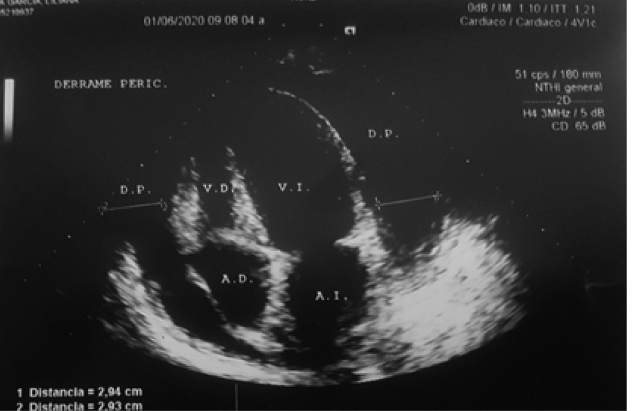

Ecocardiografía bidimensional y Doppler (01/06/2020): función diastólica de ventrículo izquierdo normal, insuficiencia mitral y tricuspídea leve, signos indirectos de hipertensión pulmonar y signos sugerentes de taponamiento cardiaco. Ver figura 3.

Se observa importante colapso de cavidades derechas; con leve retardo y diástole disminuida, se advierte bamboleo apical, signos sugerentes de taponamiento cardiaco. Además de derrame pericárdico. Fuente: Resultados del estudio.

Figura 3